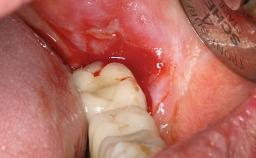

A 30-year-old female patient was referred to the Department of Periodontology of the University of Bern, Switzerland, by a dentist in private practice. Tooth 45 had been congenitally missing and had been replaced with a titanium implant three years prior to the first visit at the Department of Periodontology. The tissue level implant had a diameter of 4.1 mm, a length of 12 mm, and a sandblasted and acid-etched (SLA) surface (Straumann® Dental Implant System; Institut Straumann AG, Basel, Switzerland). The metal-ceramic crown on implant 45 had been cemented permanently. Implant 45 had been diagnosed with peri-implantitis by the referring dentist in the course of regular supportive care.

Peri-implantitis Modified by Submucosal Excess of Cement: Regenerative Peri-implantitis Therapy and Six-year Follow-up